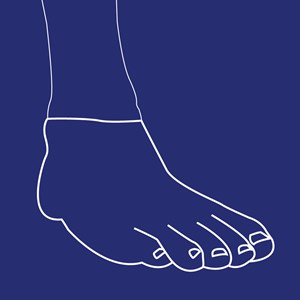

Ankelprotese (AD protese)

Type: pdf

Størrelse: 1266 KB